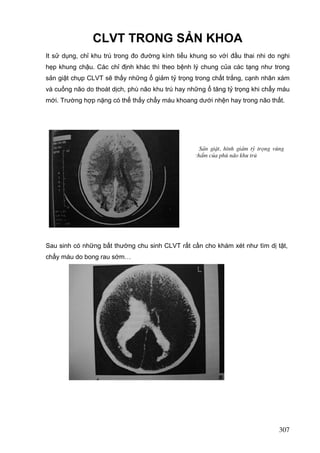

It sử dụng, chỉ khu trú trong đo đường kính tiểu khung so vớí đầu thai nhi do nghi

hẹp khung chậu. Các chỉ định khác thì theo bệnh lý chung của các tạng như trong

sản giật chụp CLVT sẽ thấy những ổ giảm tỷ trọng trong chất trắng, cạnh nhân xám

và cuống não do thoát dịch, phù não khu trú hay những ổ tăng tỷ trọng khi chẩy máu

mới. Trường hợp nặng có thể thấy chẩy máu khoang dưới nhện hay trong não thất.

S¶n giËt, h×nh gi¶m tû träng vïng

chÈm cña phï n·o khu tró

Sau sinh có những bất thường chu sinh CLVT rất cần cho khám xét như tìm dị tật,

chẩy máu do bong rau sớm…